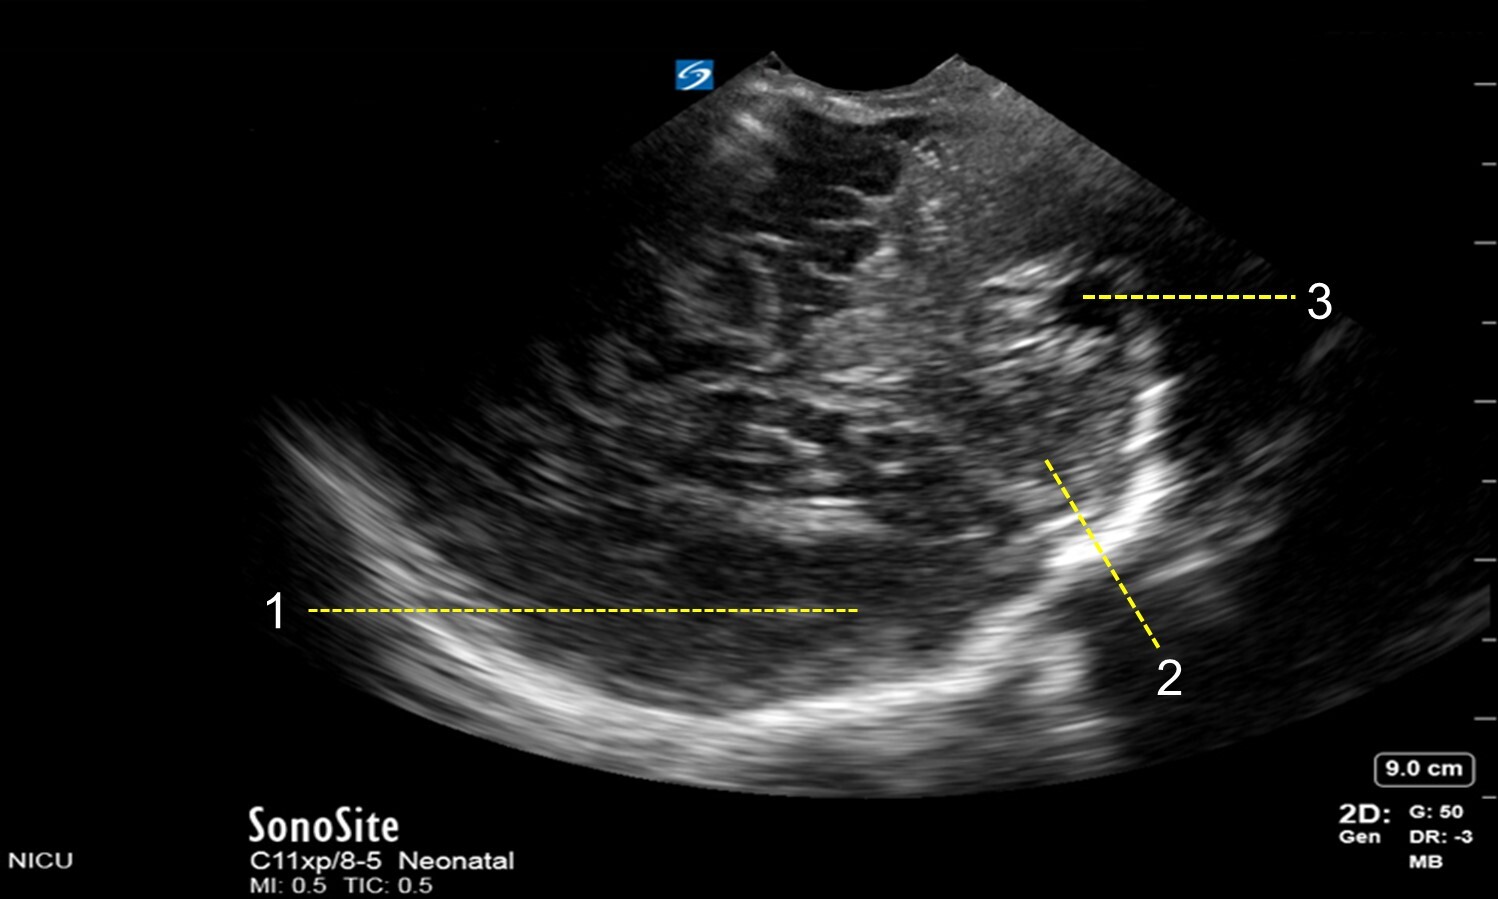

Neonatology Mastoid Fontanel – Posterior Coronal View Image

1. Parietal Lobe

2. Cerebellar Hemisphere

3. Cisterna Magna